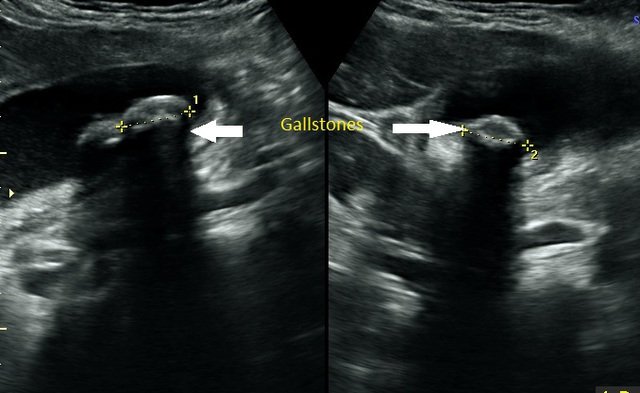

An ultrasound picture of the gallbladder with a gallstone within it.

Abdominal ultrasound scans are provided for patients who experience pain above the navel and in the stomach area. The scan is performed to examine organs in the abdomen, including the liver, gallbladder, pancreas, aorta, spleen, and kidneys. The procedure detects gallstones, cysts, and tumours, alongside other pathologies.